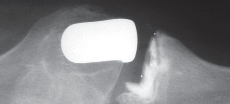

التصوير الطبي

التصوير الطبي ضروري لتأكيد التشخيص وتحديد مدى تلف المفصل:

-

الأشعة السينية العادية (Plain Radiographs):

- المنظر الأمامي الخلفي (AP): يُظهر الركبة من الأمام.

- المنظر الجانبي (Lateral): يُظهر الركبة من الجانب.

- المنظر الخلفي الأمامي المثني (PA Flexed): يسمح بتقييم أفضل للجزء الخلفي من الركبة وقد يكشف عن تغيرات أكبر في الحجرة الخلفية الوحشية.

- منظر شروق الشمس (Sunrise/Patellofemoral): لتقييم المفصل الرضفي الفخذي.

- الأشعة السينية الطويلة للطرف السفلي بالكامل (Full-length standing radiographs): من الورك إلى الكاحل، وهي مفيدة جدًا، خاصة إذا تم استخدام تقنيات الملاحة الحاسوبية. تُظهر هذه الأشعة المحاذاة الكلية للطرف السفلي.